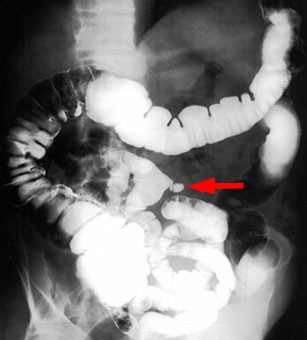

Pediatric Radiology > Abdominal > Lower GI > Meckel's Diverticulum

Meckel's Diverticulum

In a

Meckel's diverticulum, there is a persistence of the omphalomesenteric

duct. The incidence is 2-3% of the population, which makes it the most

common anomaly of the gastrointestinal tract. The majority of patients

will be under the age of ten, with a male to female ratio of 3:1. It is normally located within the last 6 feet of ileum with 94% of cases

on the antimesenteric border. |